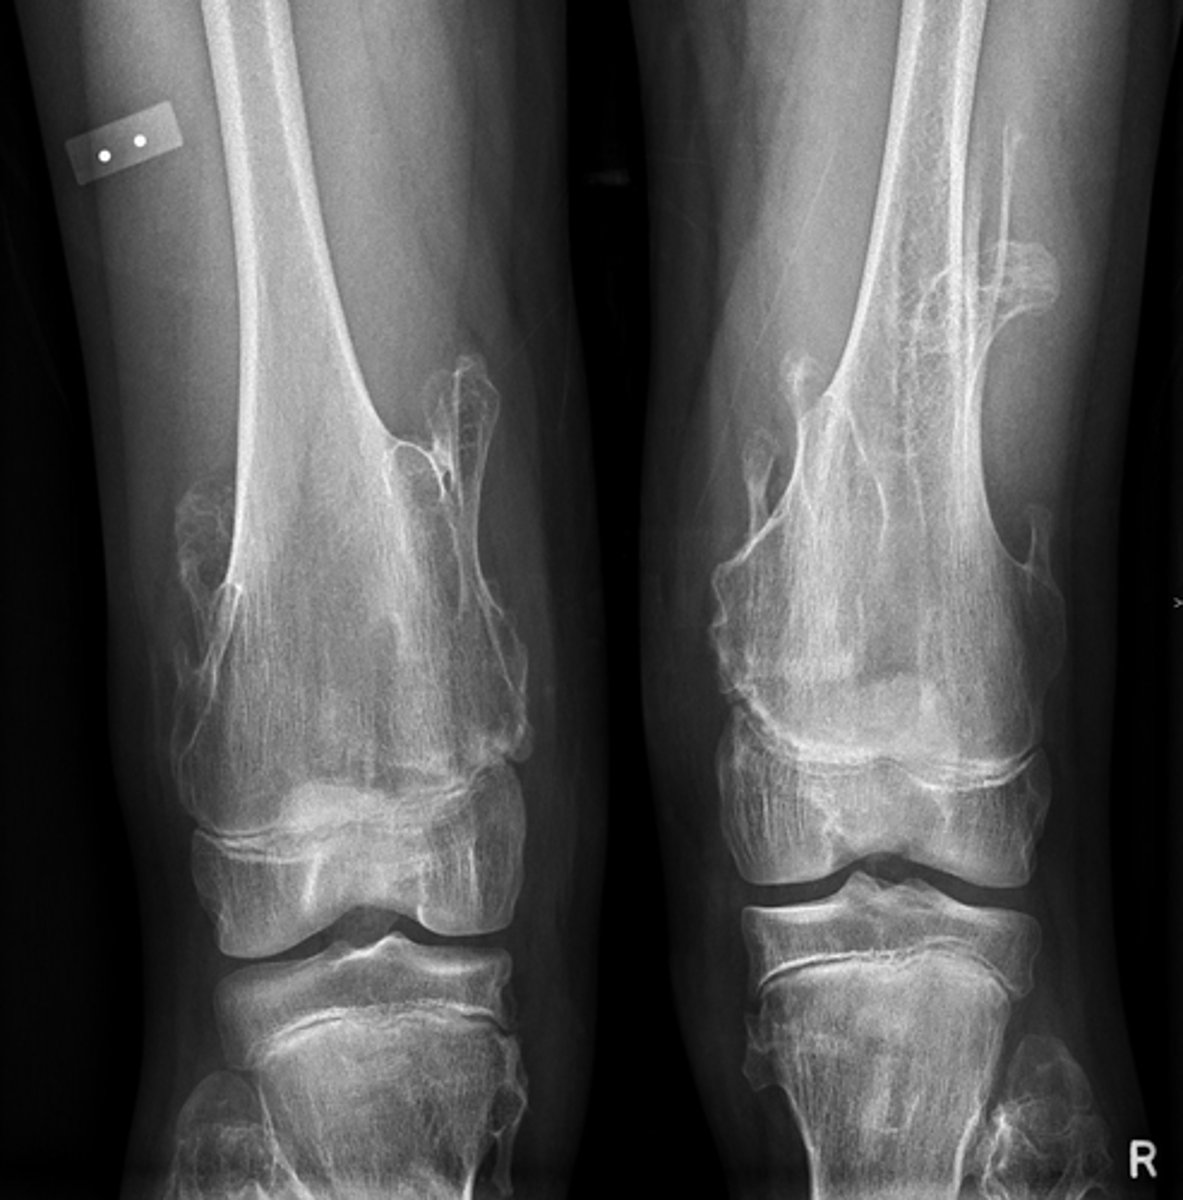

Multiple enchondromas (Ollier's disease)

Diagnosis?

<p>Diagnosis?</p>

49

New cards

- Malignant transformation (10-50%)

- Fracture

Concerns/complications?

<p>Concerns/complications?</p>

50

- Flocculent calcification

- Metaphysis/diaphysis

- Enchondroma

- Cartilaginous matrix

Describe the lesion

<p>Describe the lesion</p>

51

Enchondroma

Most likely diagnosis?

<p>Most likely diagnosis?</p>

52

Malignant transformation (rare)

53

Refer to orthopedist

Next step?

<p>Next step?</p>